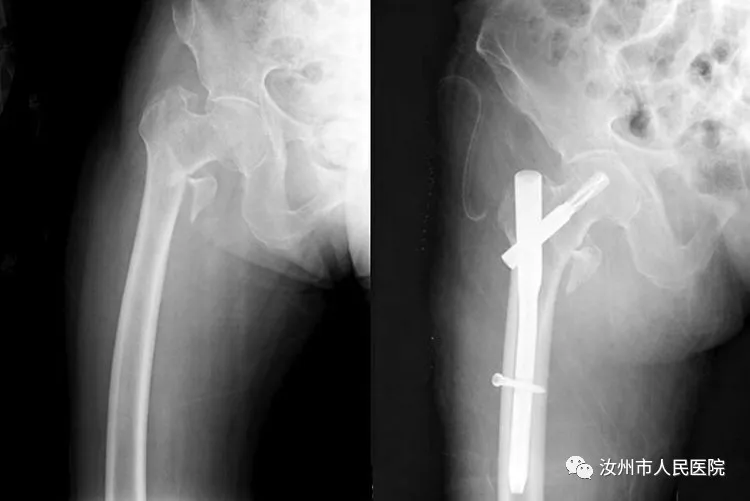

粗隆间骨折多应用PFNA微创治疗。

微创手术极大减少创伤,降低手术风险。